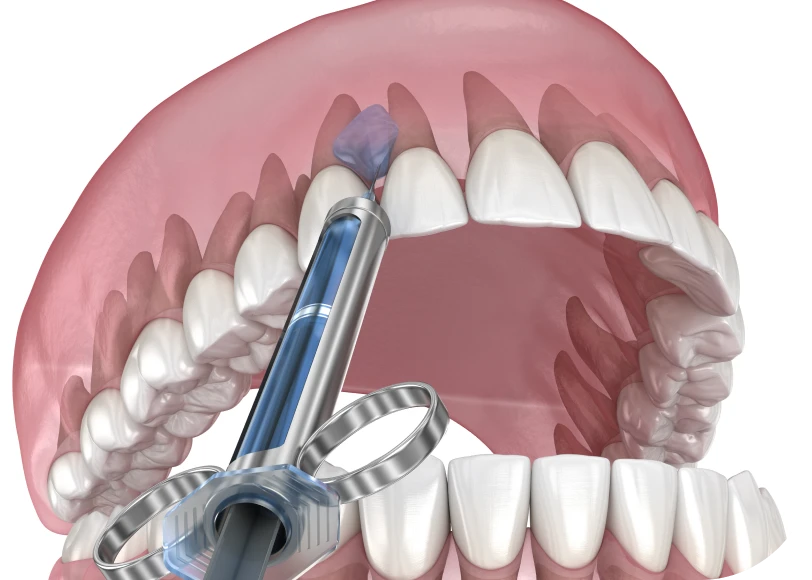

- Réalisation de l’injection

Le dentiste injecte le produit avec une aiguille fine ou une canule. Il agit avec précision, couche par couche. Il adapte la pression, le rythme et la profondeur en fonction du tissu ciblé. La séance dure entre 15 et 30 minutes. Puis, il masse doucement la zone, afin de répartir le produit de manière homogène.